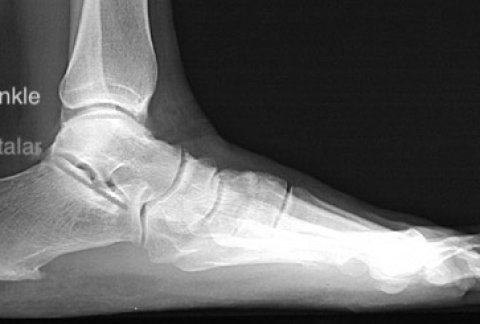

What scan do I need for my painful foot?

Within the domain of foot and ankle treatments, accurate diagnosis plays ...